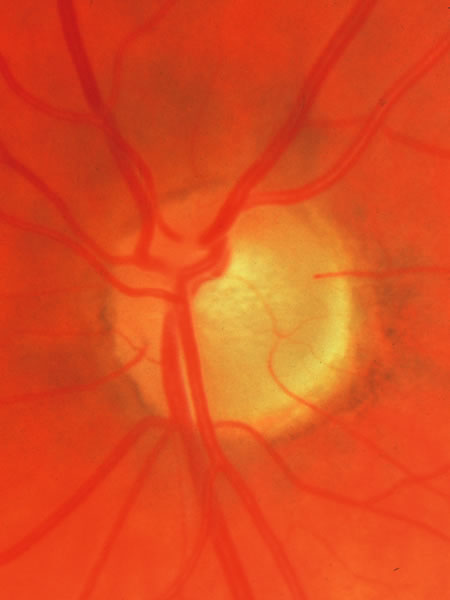

In acute angle-closure glaucoma (Fig. 33), the optic disc may swell,147–149 perhaps as a result of ischemia, but because of corneal edema and preoccupation with the angle status, it is not often seen. Even after an attack lasting several days, there is often no visual loss; the disc may remain normal appearing or may develop some degree of pallor resembling that of nonglaucomatous optic atrophy.150–152 Excavation of the disc does not seem to result from an acute attack but may result from persistent residual pressure elevation after the attack. If excavation is already present at the time that a patient presents with symptomatic angle closure, the cupping is evidence that for some time an asymptomatic, perhaps gradual, rise of intraocular pressure elevation preceded the abrupt onset of symptoms.

Fig. 33. Swollen disc tissue during an acute attack of angle closure glaucoma.